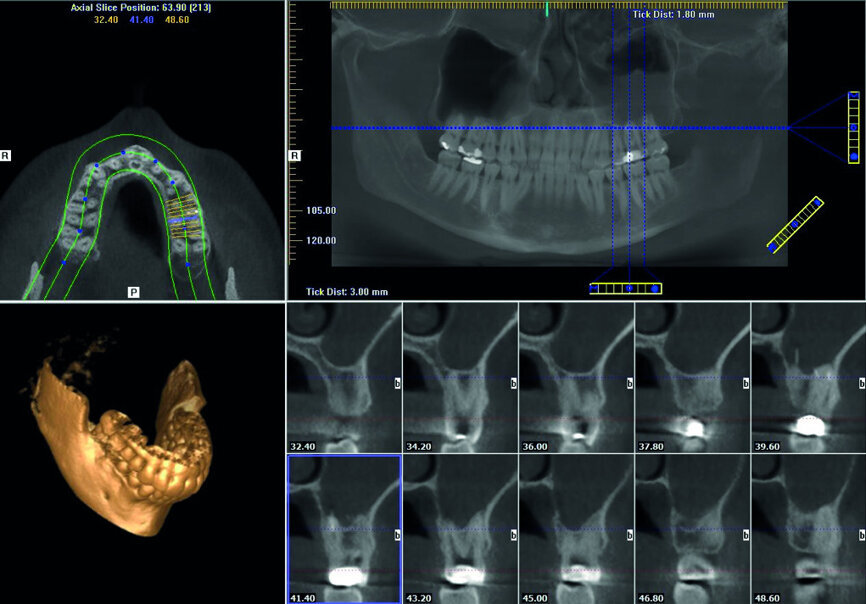

The patient was referred for a dull pain affecting a maxillary molar. On the preoperative radiograph, we could see a diversity of obturation materials, including single cones, resin cement and silver cones, with some of them already fragmented and one piece protruding from the root. Looking closely at the sinus and the sinus membrane, we could see that the membrane had been perforated by the inflammatory/infection process, which had led to sinus infection (Fig. 15).

Under the operating microscope and using ultrasonic and K3XF rotary files (Kerr Dental), I managed to clear the root system of all the previous obturation materials, and placed a dry cotton pellet and temporary cement, as the patient had become tired during this long appointment (Fig. 16). Figure 17 shows some minor debris of silver cones that had passed beyond the mesial apex and using the MacroCannula of the EndoVac, I managed to retrieve one small piece of the silver cone and to complete the chemical cleaning of the root canal system.

Figure 18 shows the immediate postoperative situation, focusing on the obturation of the mesial canals, and a slight improvement of the membrane and the sinus is evident. Figure 19 shows the three-month follow-up with an almost complete closure of the membrane and the bone of the sinus floor.